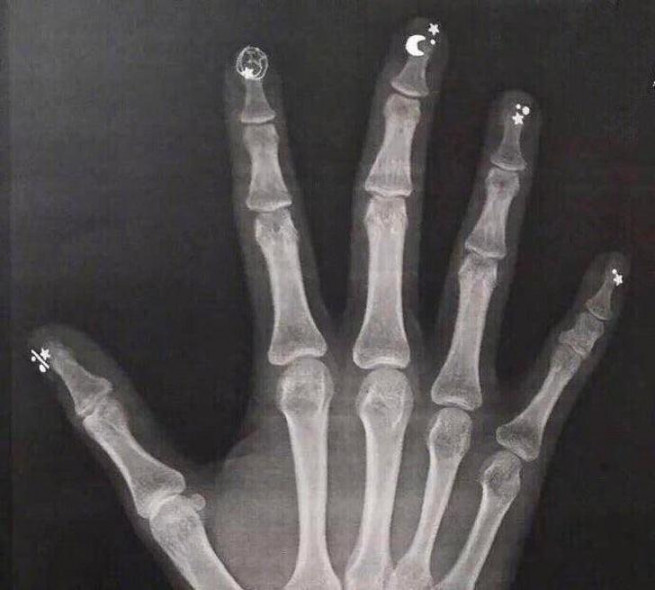

Рука с маникюром под рентгеновскими лучами

Рентгенография руки, смоченной в йоде. Йод поглощает рентгеновские лучи и подсвечивает кожу вокруг костей, отчего она кажется прозрачной